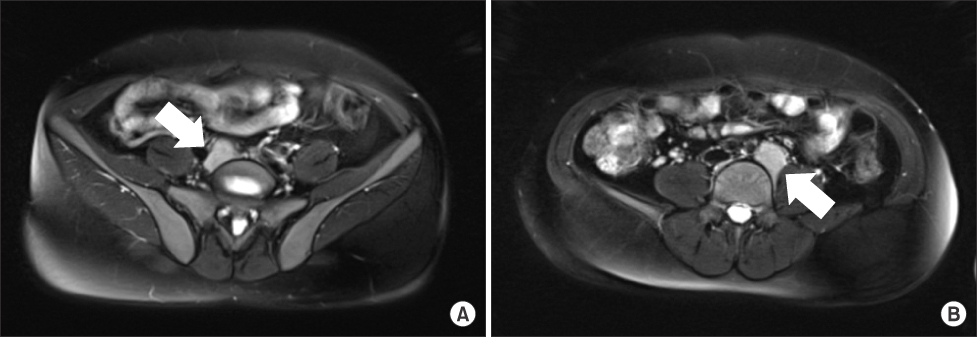

Fig. 2

Technetium-99m RBC scintigraphy shows uptake in both common iliac area masses. (A) Right side. (B) Left side.

Fig. 2 Technetium-99m RBC scintigraphy shows uptake in both common iliac area masses. (A) Right side. (B) Left side.